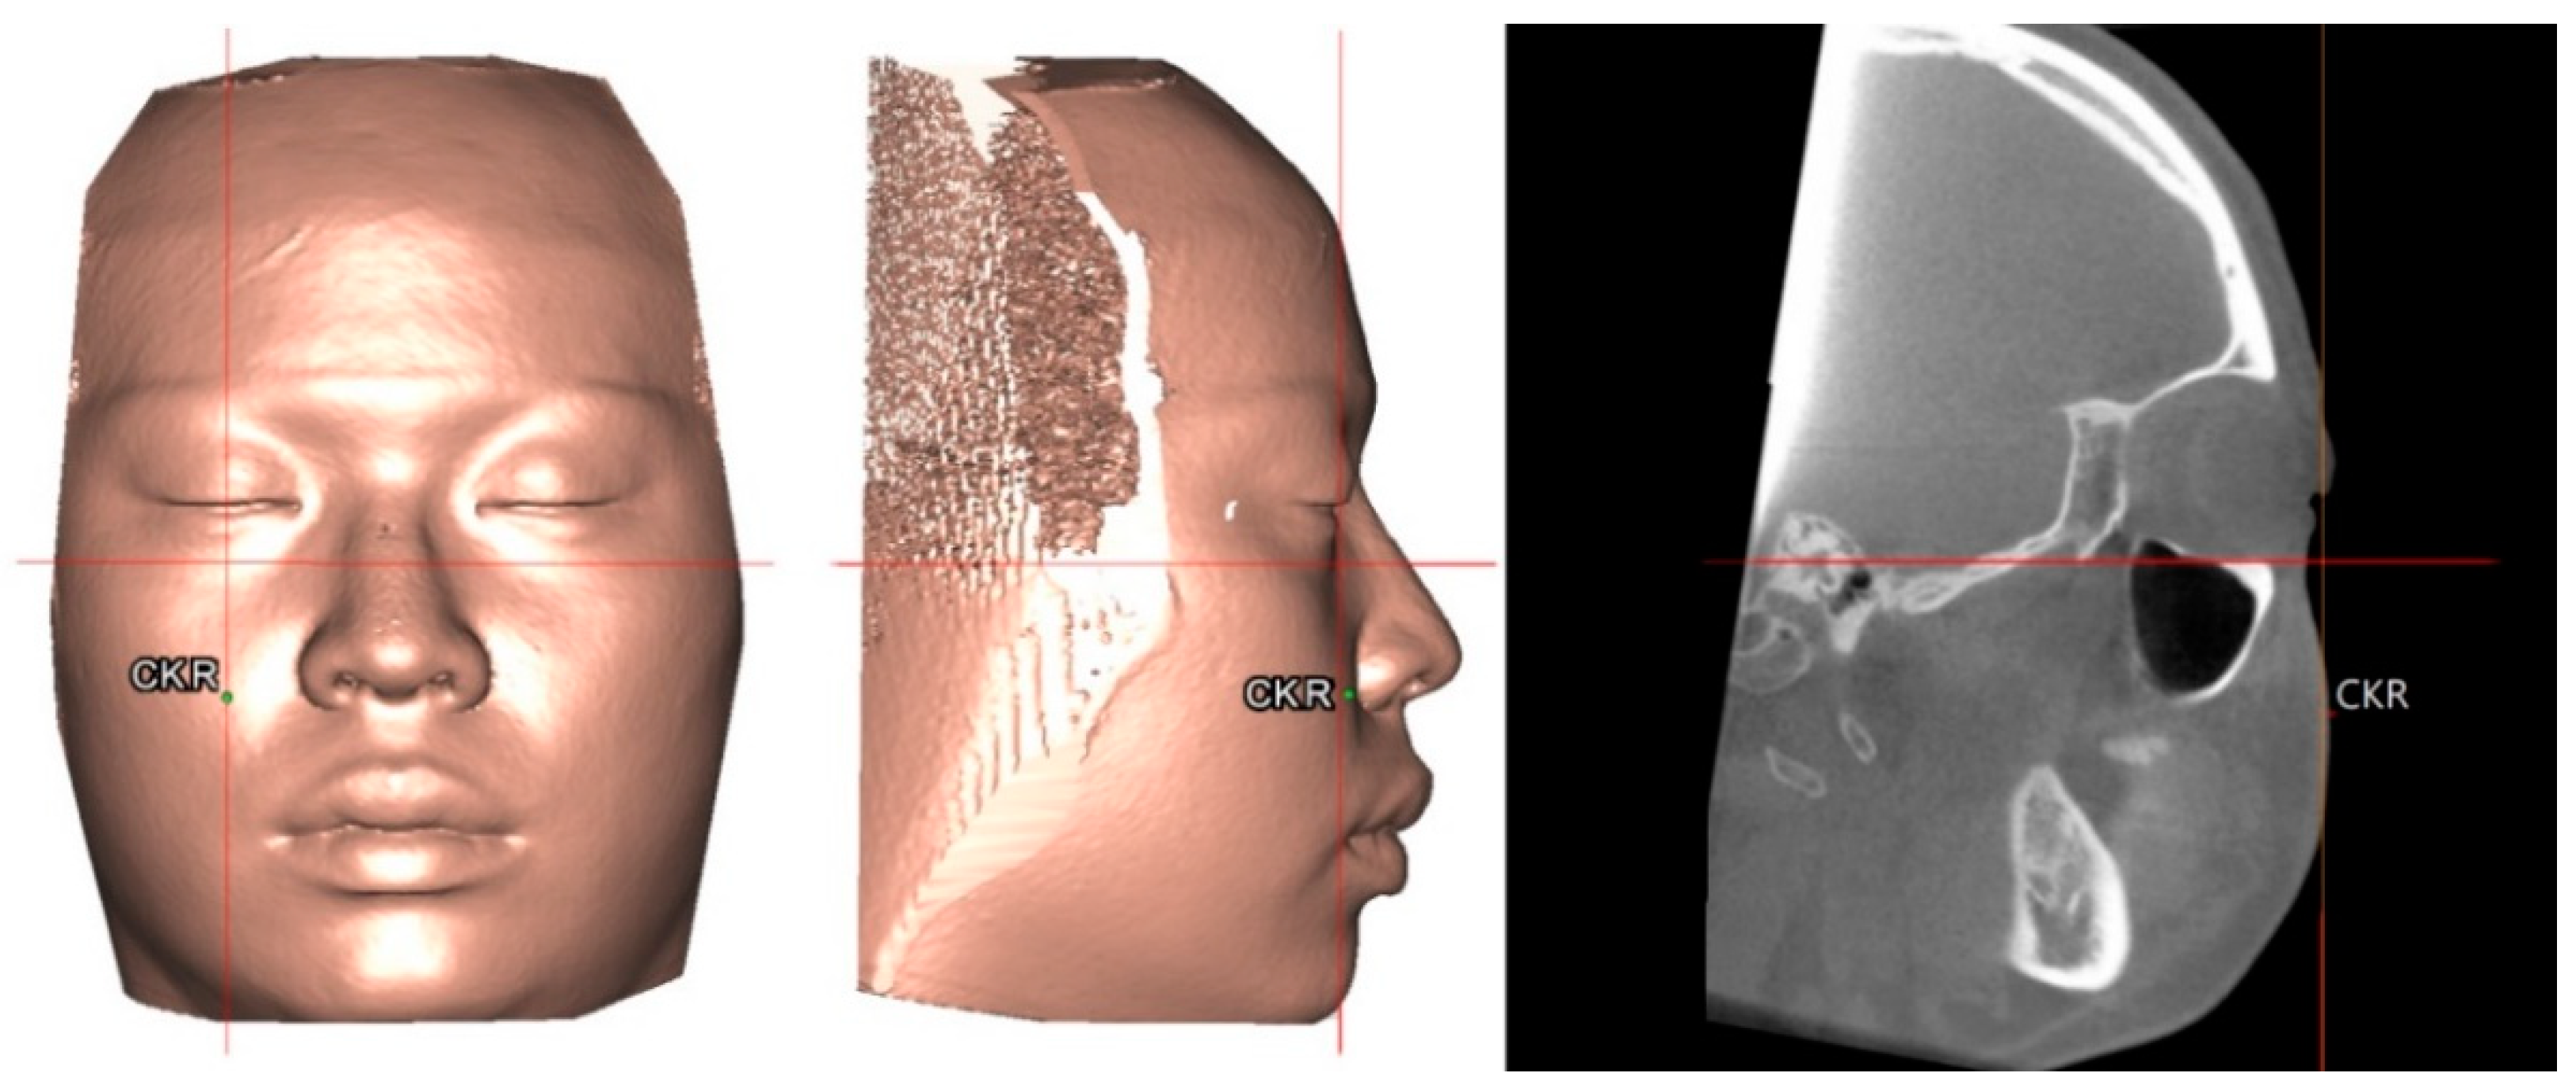

To set a normative database of 3D Burstone cephalometric measurements for Taiwanese Chinese, a total of 27 linear and nine angular measurements were generated using Simplant software. For this, all craniofacial bone and soft-tissue anatomical landmarks and reference planes (22, 14, and 8 parameters, respectively) were standardized based on previous descriptions (Table 1 and Table 2, Figure 2 and Figure 3) [11,12,33,34,35]. Two Burstone analysis-related anatomical landmarks (i.e., PtM and Ar) [11,12] were adapted; the anterior base length (S-N) replaced the cranial base length (Ar-PtM-N) and the Co-Go replaced Ar-Go for ramus length measurement. Due to the relevance of cheek prominence for overall aesthetic balance in Asians [25,36,37,38], a further parameter—that is, cheek mass (CK) (Figure 4)—was added to the Burstone soft-tissue analysis.

Figure 4. Location of cheek mass (CK) for cheek prominence measurement. To represent the most projected point on the cheek contour, the CK point was located on the most convex point on the mid-pupillary plane (vertical line) below the infraorbital area. The horizontal distance between CK and mid-pupillary vertical line was measured. For definitions, please, refer to Table 1 and Table 2.